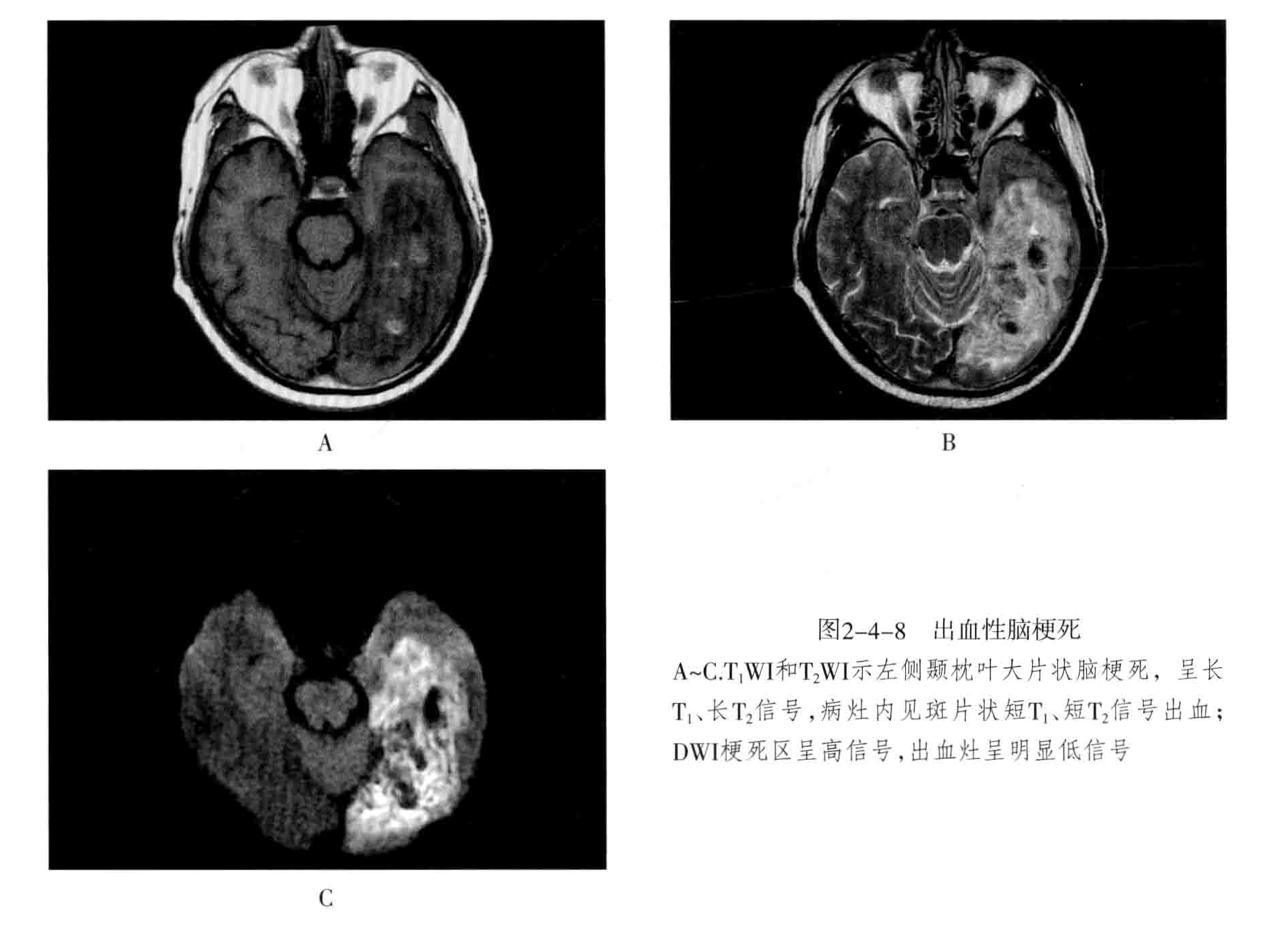

八、脑梗死:是一种缺血性脑血管疾病,常见有动脉闭塞性梗死和腔隙性脑梗死。主要病因为脑的大或中等管径的动脉发生粥样硬化,继发血栓形成,导致管腔狭窄、闭塞。以大脑中动脉闭塞最常见。脑梗死发生4-6小时脑组织发生缺血与水肿,继而脑组织出现坏死。1-2周后脑组织水肿逐渐减轻,坏死脑组织液化,梗死区出现吞噬细胞浸润,清除坏死组织,同时有胶质细胞增生和肉芽组织形成,8-10周后形成含液体的囊腔即软化灶。少数缺血性脑梗死在发病24-48小时后可因再灌注而发生梗死区内出血,转为出血性脑梗死。常见症状为偏瘫和偏侧感觉障碍、偏盲、失语等。

- CT表现为脑组织内低密度灶,梗死后2-15天为脑水肿高峰期,此时可有脑水肿表现;梗死1个月以后,相邻部位的脑室、脑池或脑沟扩大,出现脑萎缩表现。增强后梗死区可出现不均匀强化,呈脑回状、条状、环状或结节状强化。梗死区强化是由于血脑屏障破坏、新生毛细血管和血液灌注过度所致。

- MRI在脑梗死6小时之内,由于细胞毒性水肿,DWI可发现高信号,此后发生血管源性水肿、细胞死亡、髓鞘脱失、血脑屏障破坏,T1与T2弛豫时间延长。梗死后期,小的病灶不显示,表现为脑萎缩,大的病灶表现为软化灶。